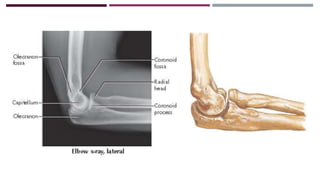

ANATOMÍA

RADIOGRAFÍA

Obtenida antes de la

reducción

Obtenida después de la